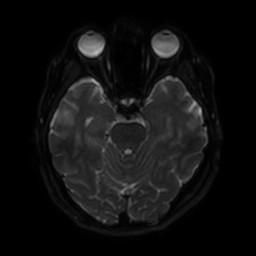

뇌 후두피질위축 봐주시면 감사하겠습니다(mri)

뇌의 위축 정도가 심한 상태인가요

요즘 눈이랑 정신이 좀 이상해서 뇌mri를 찍었는데 이렇게 나오네요.

알츠하이머와 관계가 있는 것 같은데..

정확한 것은 정식 판독을 받아보아야 알 수 있겠습니다만, 개인적인 경험을 토대로 보았을 때에는 위축이 심하다고 보기에는 무리가 있어 보입니다. 뇌실이 비정상적으로 커져 보이지도 않고 뇌의 태두리가 두개골에서 많이 떨어져 있지도 않은 것이, 해당 사진들만 보아서는 위축이 심하고 치매를 의심하여야 한다 어떻다 판단을 내리기는 어려울 것으로 사료됩니다.

특별한 이상은 보이지 않는 것 같습니다.

알츠하이머의 경우 뇌MRI로 진단하지는 않습니다.